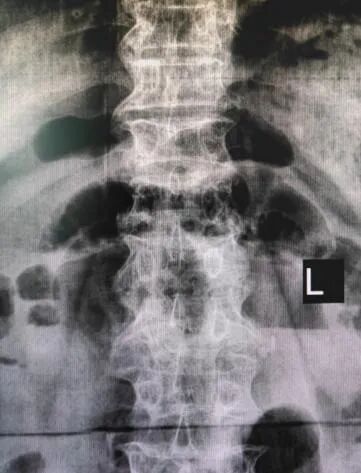

病例回顧 骨折部位 術(shù)中C臂協(xié)助定位 在C-臂監(jiān)視器透視下,分別定位胸12雙側(cè)椎弓根位置,標記穿刺點,僅以穿刺點為中心做3mm切開,在透視下注入骨水泥,再次透視見骨水泥位置良好。 骨水泥注入 術(shù)后影像學檢查 手術(shù)切口1cm左右 該手術(shù)經(jīng)皮透視下穿刺,手術(shù)切口小,創(chuàng)傷小,無需縫合,術(shù)后患者即感腰部疼痛明顯減輕,第二天可下床行走,已無腰痛不適,張大娘非常高興,自己再也不會受腰痛折磨整日與床為伴了。 我院脊柱骨科近年來,已成功開展多臺PVP手術(shù),為廣大老年患者減輕了病痛,減少了患者臥床時間,提高了生活質(zhì)量,是骨質(zhì)疏松性椎體骨折患者的福音。如果家里的老人突然出現(xiàn)了腰背疼痛,翻身下床困難,或者出現(xiàn)了腹部不適,排除腹部疾病(因為很多胸腰椎骨折患者在早期以腹痛腹脹為最主要癥狀),無論有沒有外傷史,建議帶老人及早就醫(yī),如果發(fā)現(xiàn)椎體損傷,積極治療,讓老人度過一個輕松愉快的晚年生活。 科普小講堂:經(jīng)皮椎體成形術(shù) 什么是骨質(zhì)疏松性椎體骨折? 骨質(zhì)疏松性椎體壓縮骨折,即在日常生活中患者并未遭受到明顯的外力而發(fā)生的骨折。這種骨折與創(chuàng)傷性的骨折不同,是由于自身骨質(zhì)疏松所導(dǎo)致的骨組織病變。骨質(zhì)疏松性骨折發(fā)生時,患者會感覺到背部明顯疼痛,翻身或起床等動作會讓疼痛更加明顯。 骨質(zhì)疏松性椎體壓縮骨折的危害有哪些? 一旦椎體發(fā)生骨質(zhì)疏松性椎體壓縮骨折,常常會導(dǎo)致患者出現(xiàn)腰背部持續(xù)性疼痛、季肋部放射痛、后凸畸形、呼吸功能受限及胃腸道癥狀等諸多癥狀,造成老年患者生活質(zhì)量下降。 什么是經(jīng)皮椎體成形術(shù)? (Percutaneousvertebroplasty,PVP)是一種新型的脊柱微創(chuàng)手術(shù),通過采用經(jīng)皮穿刺的方法,經(jīng)過椎弓根或是直接向椎體中注入骨水泥,使得椎體的強度和穩(wěn)定性得以提升,防止塌陷,從而達到緩解腰背疼痛,甚至部分恢復(fù)椎體高度的目的。 PVP手術(shù)優(yōu)點是什么? 1.恢復(fù)顯著:通常術(shù)后6個小時即能達到穩(wěn)定固定,患者可下床站立活動,大大縮短了患者臥床的時間。 2.疼痛減輕:術(shù)后患者會發(fā)現(xiàn)腰背部疼痛明顯減輕。 3.微創(chuàng):該治療方法僅需在皮膚上留2-3mm的穿刺針孔。 4.安全性:由于手術(shù)采用的是局部麻醉,因此即便是存在多種基礎(chǔ)病的患者也能夠耐受手術(shù),整個手術(shù)過程相對安全。 就診地址 酒泉市中醫(yī)醫(yī)院四樓脊柱骨科 咨詢電話 一樓門診部:0937-2669161 王醫(yī)生:13209409826 ??? 張醫(yī)生:18219971722